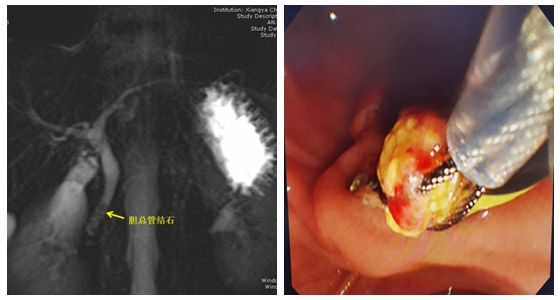

近期,湘雅常德医院普外一区(肝胆胰外科)成功开展了湘西北首例ERCP(经内镜逆行性胰胆管造影术)序贯单孔腹腔镜胆囊切除术,以ERCP治疗胆总管结石、单孔腹腔镜胆囊切除治疗胆囊结石的两个超微创术式整合方案成功为李先生解决了胆囊结石、胆总管结石的疾患。出院时,李先生看着肚脐上2cm左右大小的隐藏疤痕很开心的说道“疤痕很小很隐蔽、切口疼痛很轻,又不需要带2个月的引流管,出院后我很快就可以投入工作啦”。

ERCP联合单孔腹腔镜胆囊切除术是将治疗胆总管结石的微创技术和治疗胆囊结石的微创技术联合,在保证安全、质量的前提下,以体表几乎无痕的方式解决病人的疾患,对于部分符合适应证的病人可以达到祛除病痛和美容的效果。